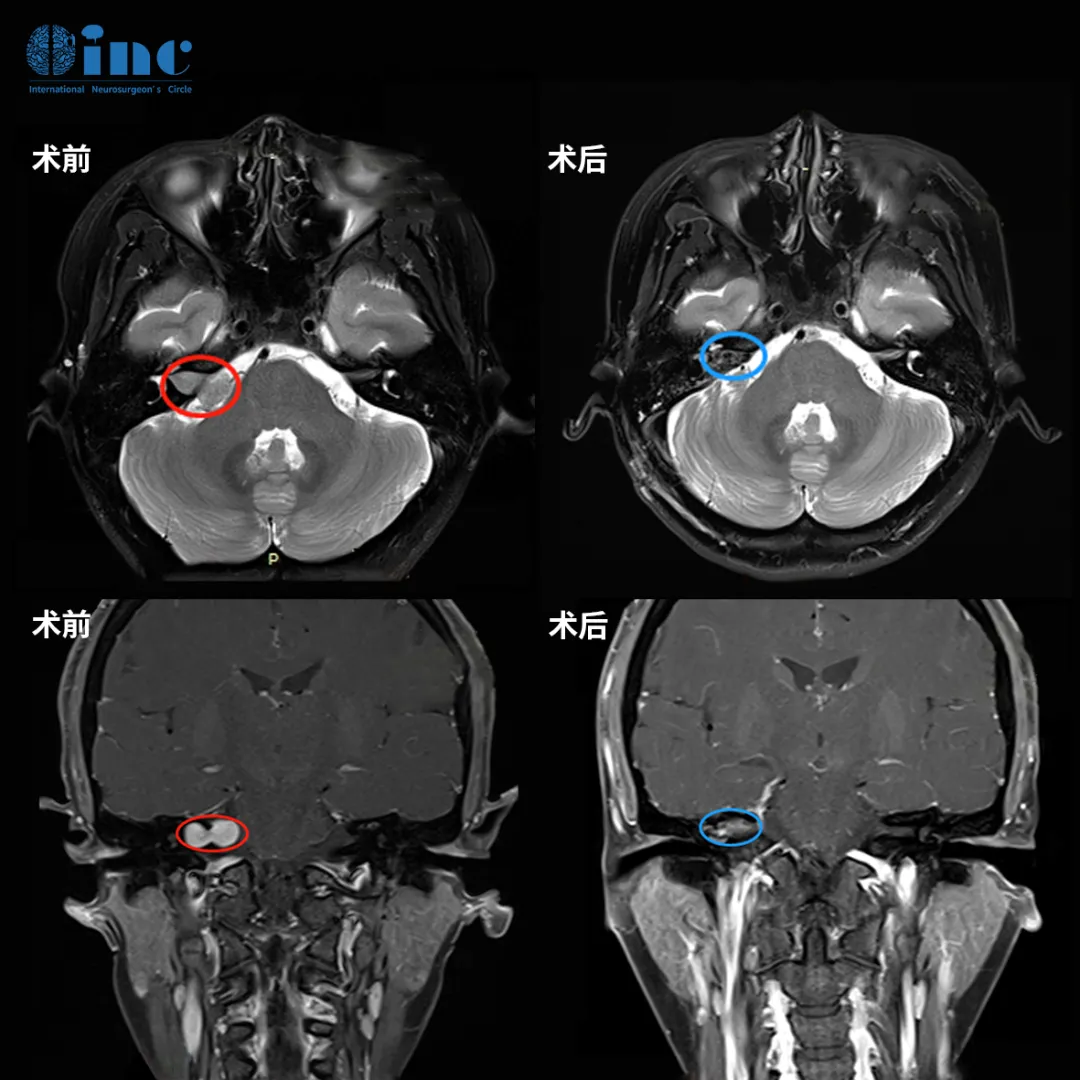

可这6年间前后发生了4次突发性耳聋,而第4次药物治疗无效后,才去了大医院进行了头颅核磁检查,结果令她震惊:听神经瘤。

医生告诉她:听神经瘤是良性肿瘤,但肿瘤位置深,靠近脑干,且与面神经粘连密切,如果手术,不仅听力保不住,面瘫的概率也极高。

因此,她找到INC巴教授为她主刀,结果令人欣慰:肿瘤不仅被完全切除,面神经也成功保留,她没有面瘫。